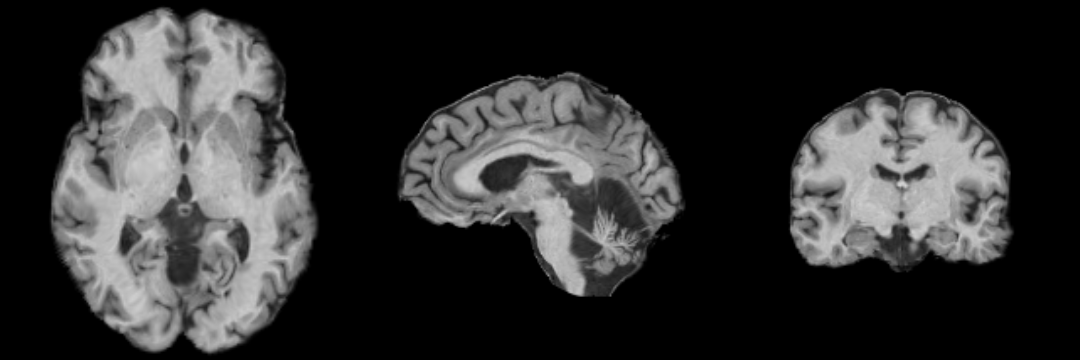

MRI Human Head pipeline for a finer-grained parcellation (TODO: Priya please provide description and proper citation)

Atlas

The atlas hes been created by Padmapriya Srinivasan and Sylvain Bouix from (PNL-BWH)

Image Dimension = 256 x 256 x 220

Image Spacing = 0.9375 x 0.9375 x 0.9375

| Template (T1) | CSF | Left Temporal GM | Left Temporal WM |